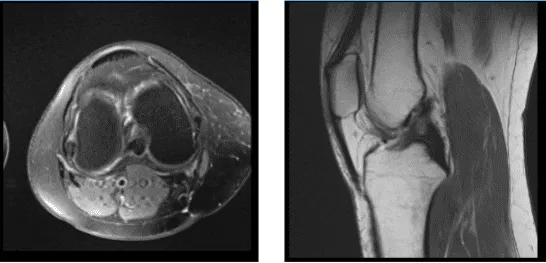

Resonancia magnética de rodilla derecha sin contraste

Se revisaron y debatieron las resonancias magnéticas; Ligamentos colaterales: El ligamento colateral medial está intacto. El ligamento colateral lateral, el tendón del bíceps femoral, la banda iliotibial y el tendón poplíteo están intactos.

Ligamentos cruzados: Los ligamentos cruzados anterior y posterior están intactos. Meniscos: Desgarro oblicuo periférico en el cuerpo y en el cuerno posterior del menisco medial. El menisco lateral está intacto. Cartílago: Las superficies condrales en el compartimento medial están intactas. Las superficies condrales en el compartimento lateral están intactas.

Fisura condral focal en la faceta patuliana medial. Hueso: Las estructuras óseas visualizadas muestran una intensidad normal de la médula ósea y la señal cortical, sin evidencia de fractura, lesión ósea trabecular o luxación. No se identifican lesiones óseas.

Mecanismo extensor: Los tendones del cuádriceps y la rótula están normales. Articulación: Pequeño derrame articular. Por lo demás, los tejidos blandos son normales. Las estructuras neurovasculares muestran un curso normal. Presenta una impresión: desgarro oblicuo periférico en el cuerpo y el cuerno posterior del menisco medial. Fisura condral focal en la faceta de rótula medial. Pequeño derrame articular.